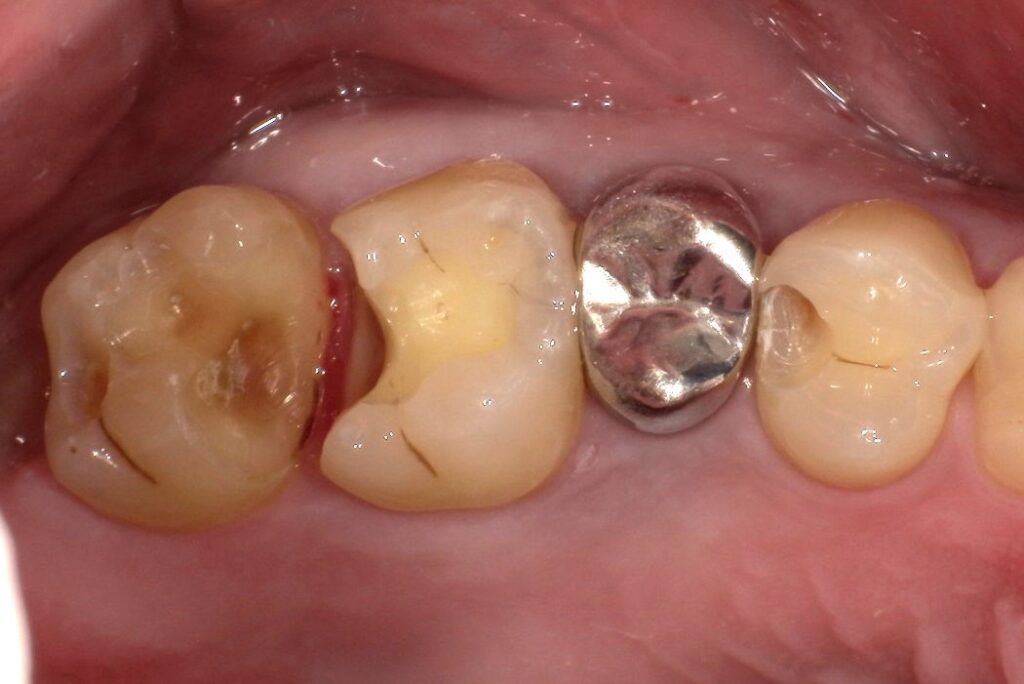

Case.01

治療前

治療後

| 主訴 | 虫歯を治したい。白く強度のあるものにしたい。 |

| 治療期間 | 1か月(3回) |

| 治療費 | 1本 ¥80,000+税 |

| 治療内容 | 右上4,5,6番目の虫歯を除去し、セラミックインレーを装着しました。 |

| 治療のリスク | 神経を温存しています。一時的に知覚過敏の症状が出ることがあります。また、咬合の強い方の場合、材料の破損の恐れがあり、夜間のマウスピースの装着をお勧めしております。 |